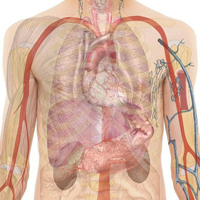

Know Your Anatomy